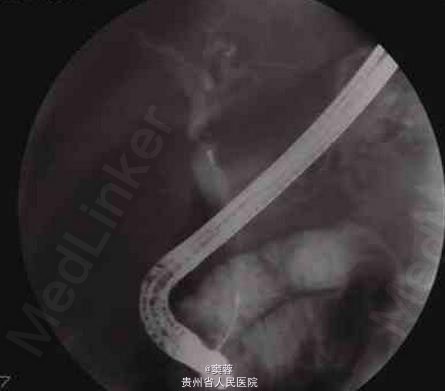

患者男性,60岁,有慢性胆囊炎及胆囊结石病史20年。患者于2006年6月中旬无诱因出现尿黄、皮肤黄,无腹痛、发热等,在当地医院接受经内镜逆行胰胆管造影(ERCP)及胆管塑料支架置入引流。ERCP造影提示患者有肝门部占位。